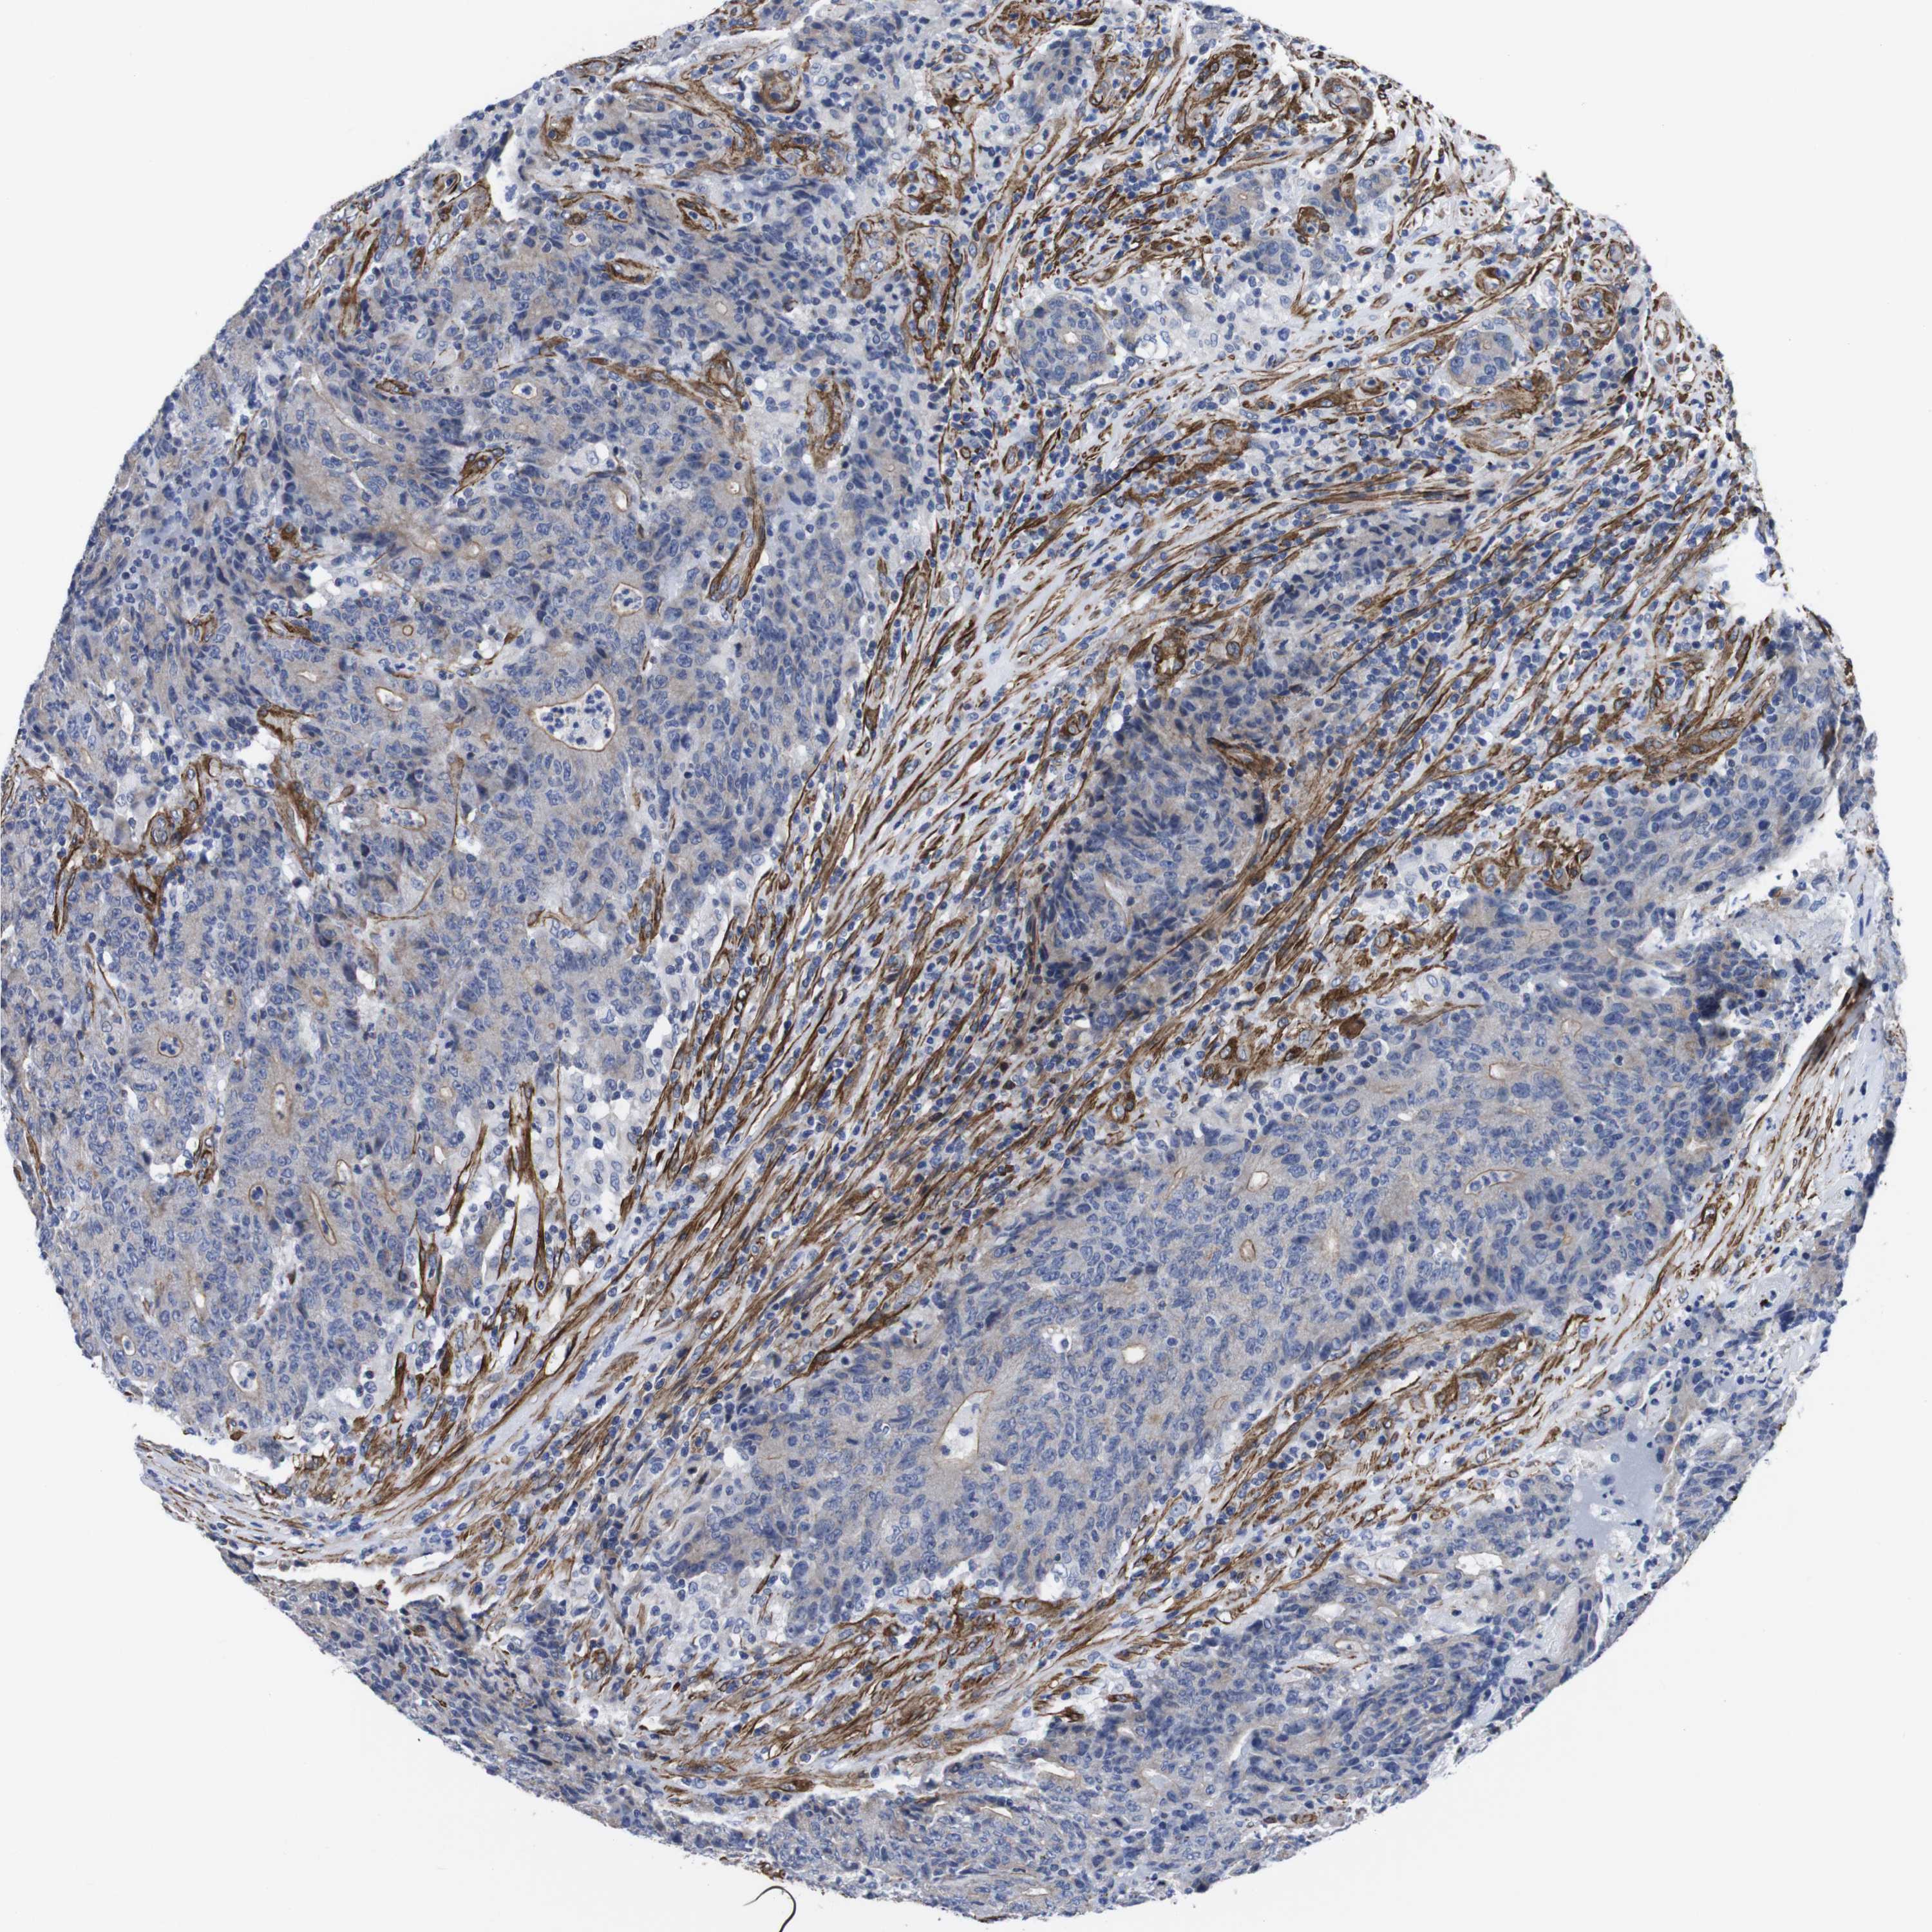

CANCER COLORECTAL CANCER Show tissue menu

Colorectal cancer

Colon adenocarcinoma